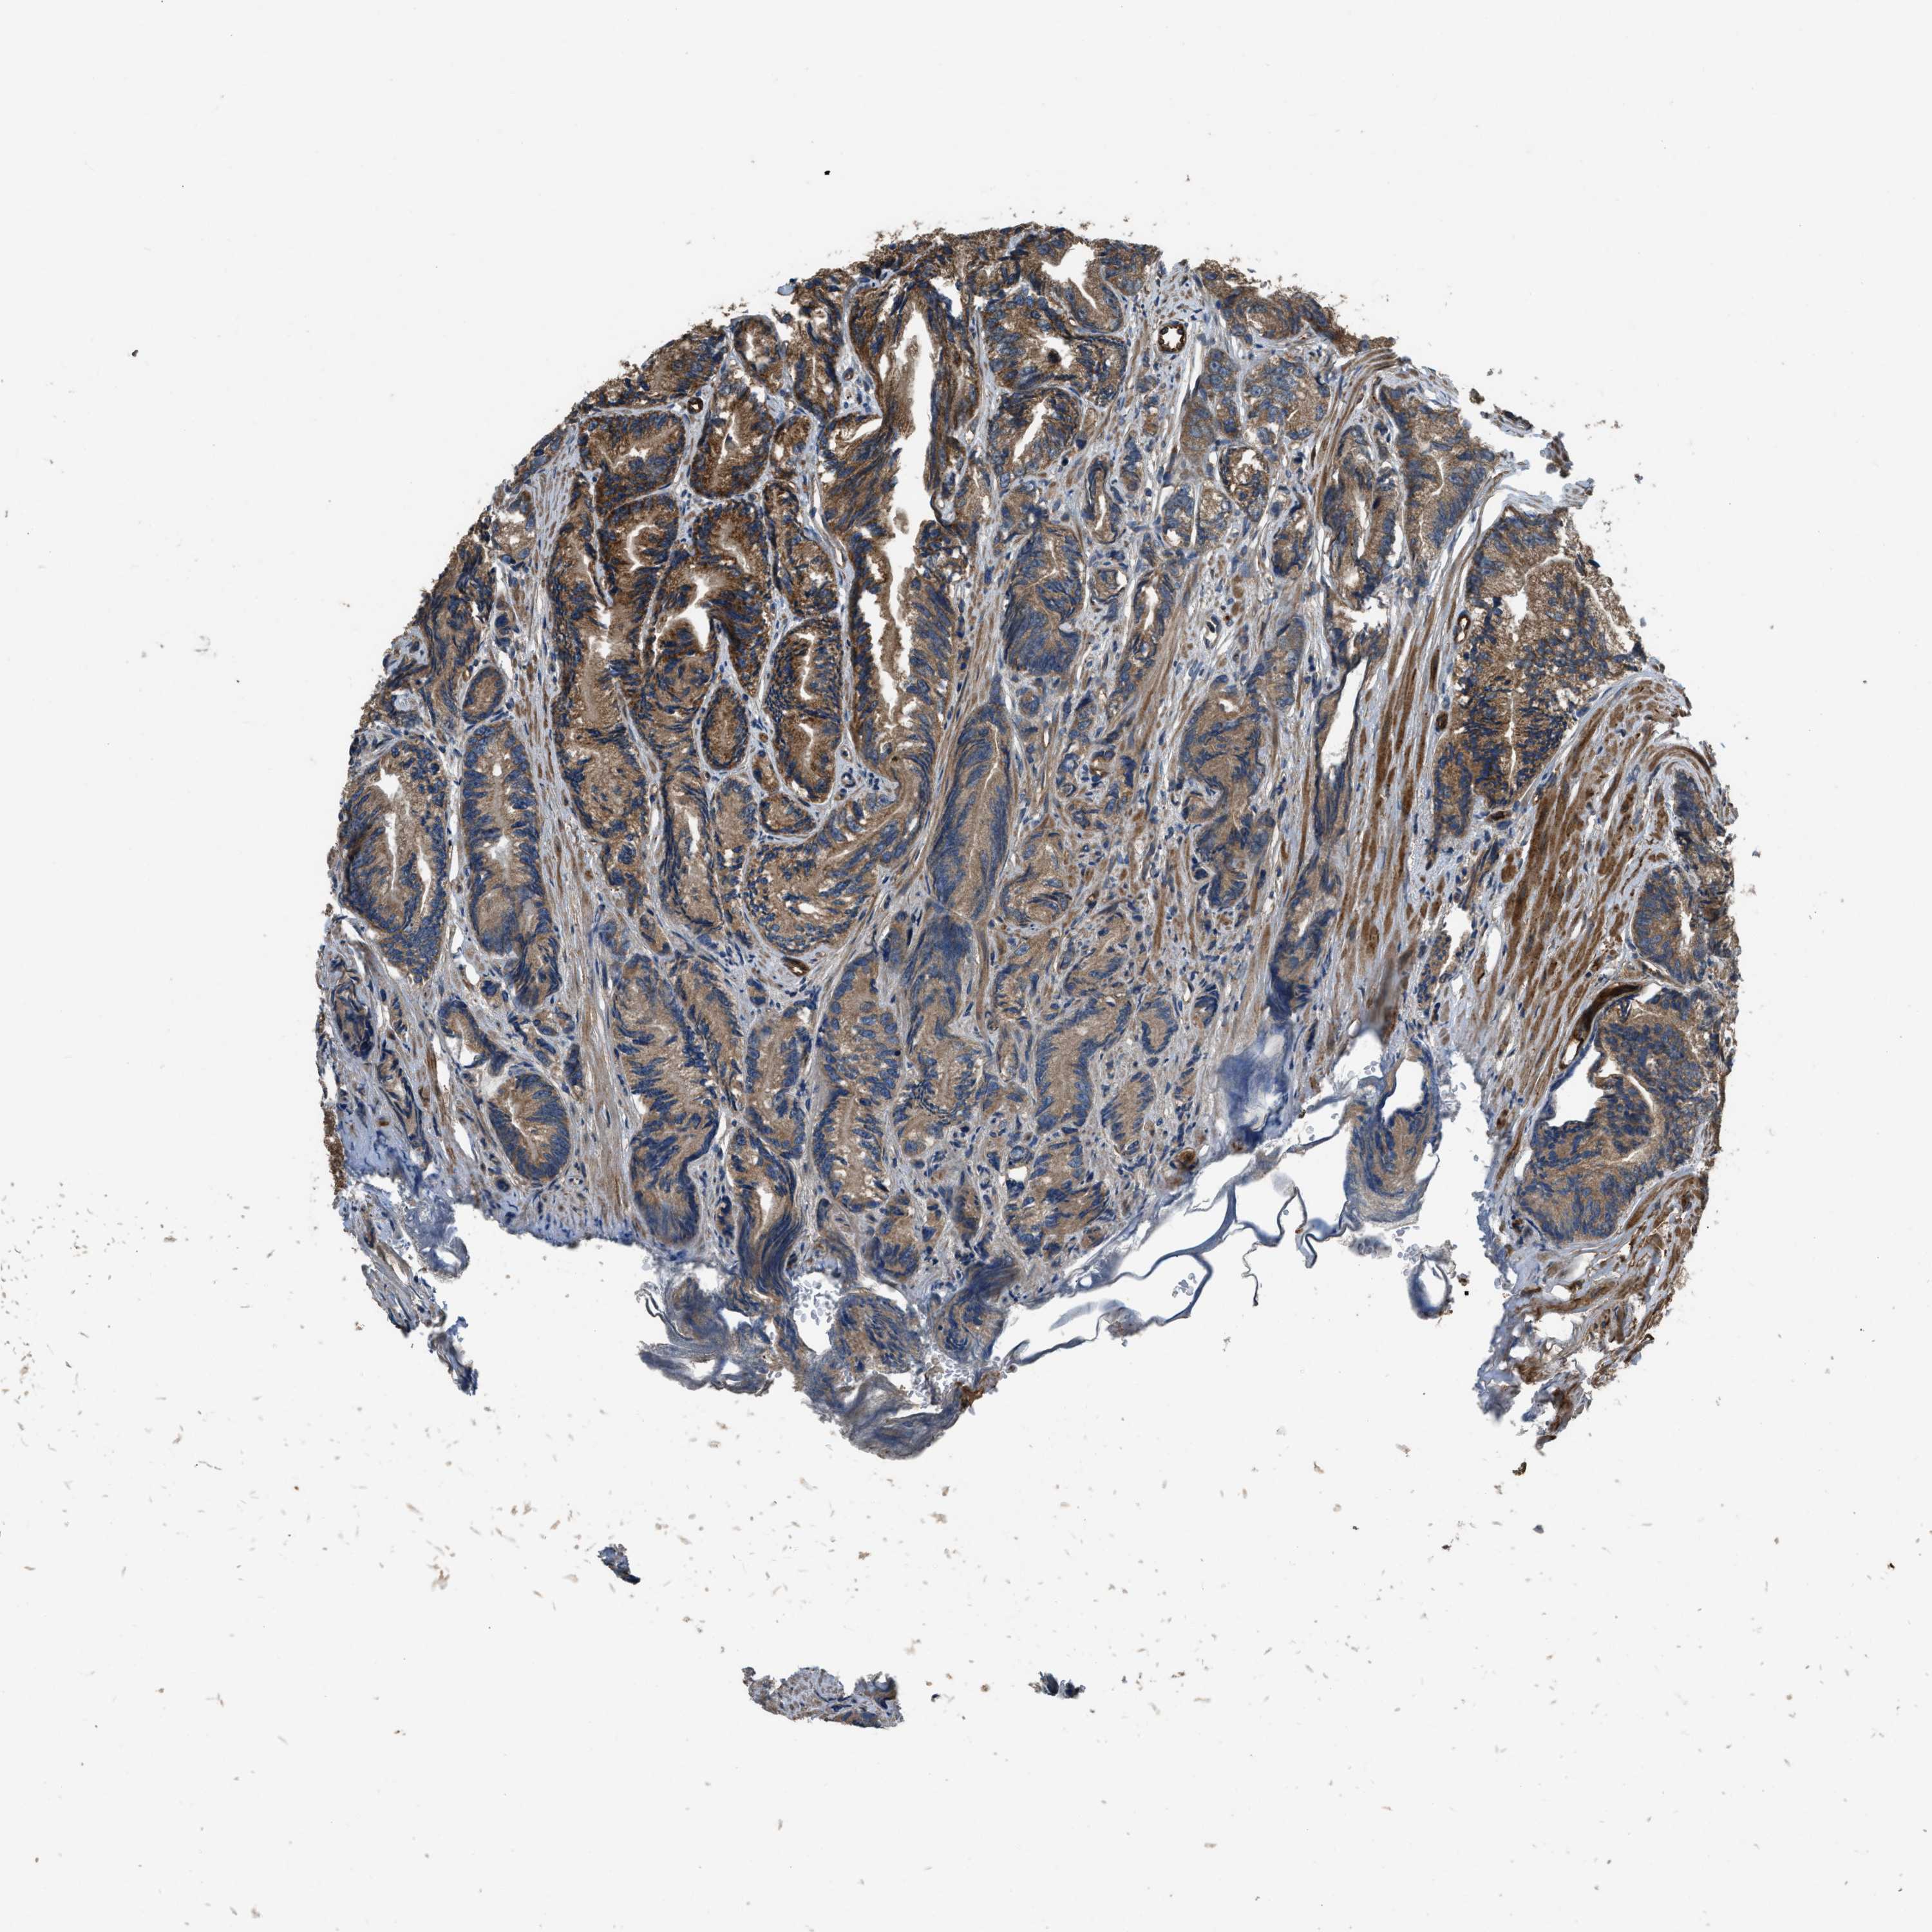

PROSTATE CANCER - Protein expressioni

A mouse-over function shows sample information and annotation data. Click on an image to view it in a full screen mode. Samples can be filtered based on level of antibody staining by selecting one or several of the following categories: high, medium, low and not detected. The assay and annotation is described here.

Note that samples used for immunohistochemistry by the Human Protein Atlas do not correspond to samples in the TCGA dataset.

Antibody stainingi

Antibody staining in the annotated cell types in the current human tissue is reported as not detected, low, medium, or high, based on conventional immunohistochemistry profiling in selected tissues. This score is based on the combination of the staining intensity and fraction of stained cells.

Each image is clickable and will lead to virtual microscopy that enables deeper exploration of all samples and also displays staining intensity scores, fraction scores and subcellular localization as well as patient and tissue information for each sample.

Antibody HPA025226

Antibody CAB019296

Staining

High

Medium

Low

Not detected

Intensity

Strong

Moderate

Weak

Negative

Quantity

>75%

75%-25%

<25%

None

Location

Nuclear

Cytoplasmic/membranous

Cytoplasmic/membranous,nuclear

Adenocarcinoma, High grade

Adenocarcinoma, Low grade